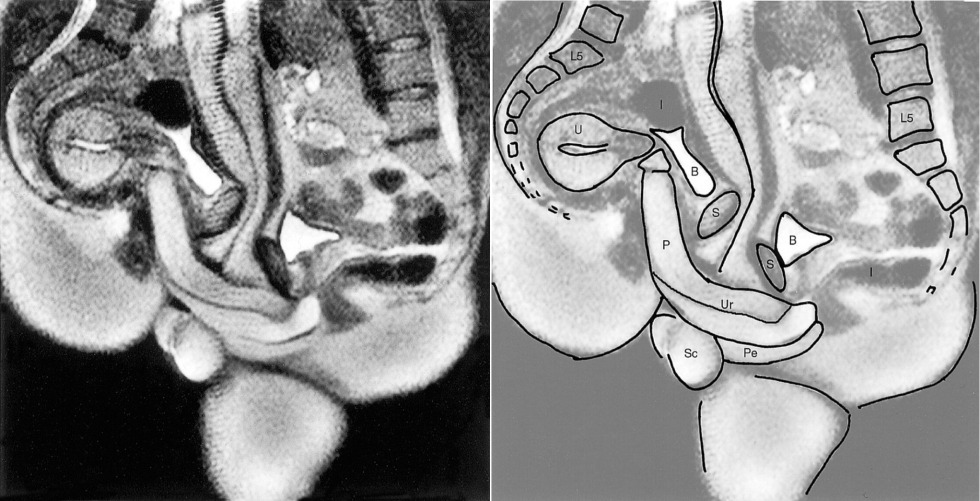

A cross-sectional diagram of the sex act in porn

Anatomy of sexual intercourse

Anatomy of sexual intercourse in the section